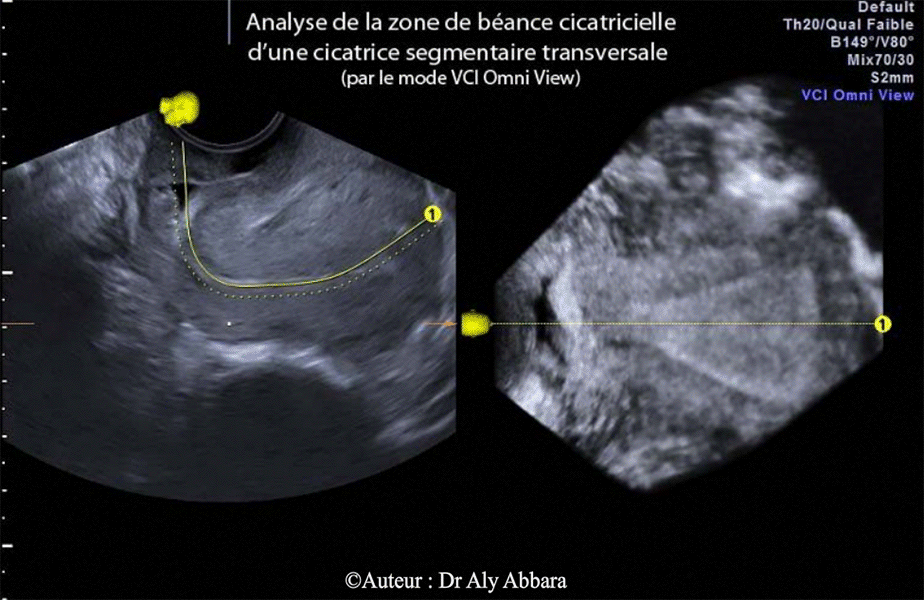

Cicatrice d'une césarienne segmentaire transversale identifiable par l'échographie 3D, mode "Omni view" ; ce mode permet d'explorer cette cicatrice dans un plan frontal tout en analysant la forme de l'utérus et de la cavité utérine.

Il s'agit d'une cicatrice béante et prenant, sur la coupe frontale la forme d'une fissure profonde et étendue sur toute la largeur de la paroi antérieure de l'isthme utérin.

En échographie 3D, mode "Triplan", la cicatrice peut être analysée sur trois coupes (sagittale, transversale et frontale).

En échographie 2D, cette zone de béance (rupture de continuité) prend la forme d'une goutte d'eau (vessie pleine) ou d'un triangle (vessie vide).